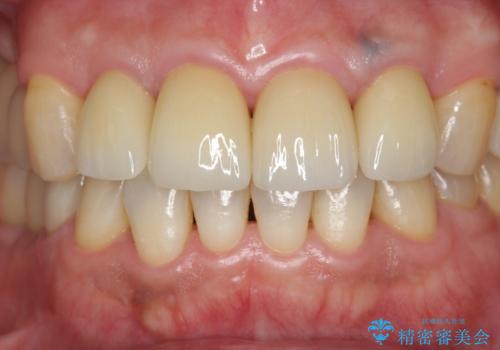

「 放置した虫歯 」 前歯セラミック治療

- 61.6万円(仮歯・ジルコニアクラウン×4・ファイバーコア ・エクストリュージョン)費用は治療当時の料金となります

虫歯の放置により、根管治療や深い虫歯に対する処置が必要になりましたが丁寧に一つづつ処置を行ったことで抜歯をすることなく歯を残すことができました。

セラミッククラウンの製作をする前に、歯内・歯周環境の整備は非常に大切です。